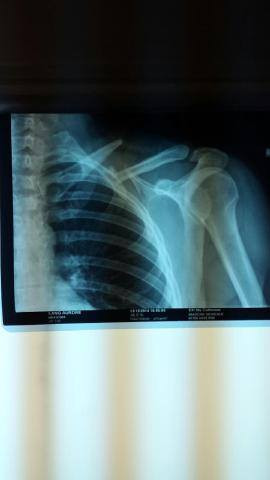

vicky2011 Oui c'est ça, ils n'opèrent que rarement car trop de risques de léser nerveusement voir d'hémorragies importantes (et effectivement 6 ans après je n'ai pas encore retrouvé la même qualité de sensation au niveau de la peau environnante et ai régulièrement des fourmillements très très agaçants vu que c'est un peu une démangeaison fantôme ), ils essaient autant que possible de réparer mécaniquement avec un cal osseux, mais dans mon cas ils ont quand même sérieusement merdé vu que dès le début il était assez flagrant que ça ne pouvait pas revenir en place mécaniquement

Stricto sensu de mémoire j'avais le "droit" de remonter dès les traits de fracture enfin comblés, mais tout en étant avertie qu'une nouvelle grosse chute pouvait faire de considérables dégâts vu que ça ne pêterais pas au niveau de l'osteosynthese mais a côté ... honnêtement j'ai tellement dégusté durant ces quelques mois et surtout avec la greffe osseuse qui s'en est suivie pour combler le bout d'os nécrosé ( du fait des mois d'attente )que je n'avais aucune envie de tenter le diable , je suis remontée au bout de quelques mois mais très occasionnellement, et refroidie , avec gilet airbag (puis projet bébé, puis elevage, donc ça a clairement marqué un tournant dans ma vie equestre , autant je n'avais pas d'appréhension de chuter avant autant désormais ce n'est plus le cas, pourtant sur le coup ça allait, c'est vraiment les mois de galère et douleur qui m'ont un peu "traumatisé"je pense ); je n'ai osé remonter sans airbag qu'une fois les broches retirées